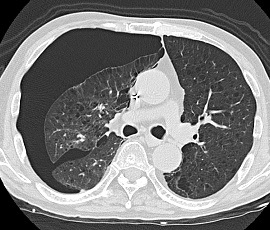

[気胸] 手術:胸腔鏡下肺縫縮術(胸腔鏡下肺部分切除術含む)

CT画像